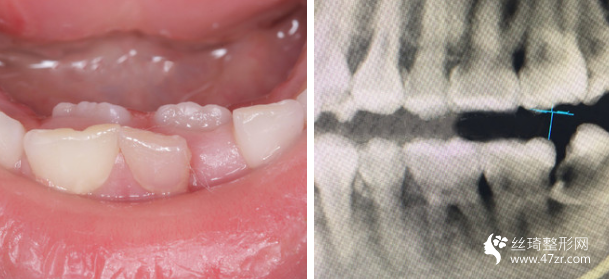

3.武漢伽美醫(yī)療美容醫(yī)院譚頔牙周病、烤瓷、牙美容行業(yè)專家案例展示

我的牙齒其實(shí)問題不大,但是下面兩個(gè)牙齒被擠的歪了出來,而且我 一直覺得我的嘴有點(diǎn)往外凸出,所以一直都有矯正的想法,朋友在他 們家做的貼面,推薦給我說薇琳醫(yī)生很專業(yè)的,所以我也就過來了。 首先做了檢測(cè),然后設(shè)計(jì)了方案,取模,然后根據(jù)自己的牙齒情況制 定矯正器。 耐心等待我矯正器的到來。

很感謝我遇到了不錯(cuò)的醫(yī)生,在這方面臨床經(jīng)驗(yàn)比較豐富,醫(yī)生說我的矯治過程進(jìn)展的較為順利,矯正速度真的是較為快呢,牙齒不齊整體也在調(diào)整牙齒咬合狀態(tài)了。

現(xiàn)在笑的時(shí)候更加自信了,所以牙弄齊了以后我打算在做個(gè)美白,平時(shí)抽煙牙齒也很黃